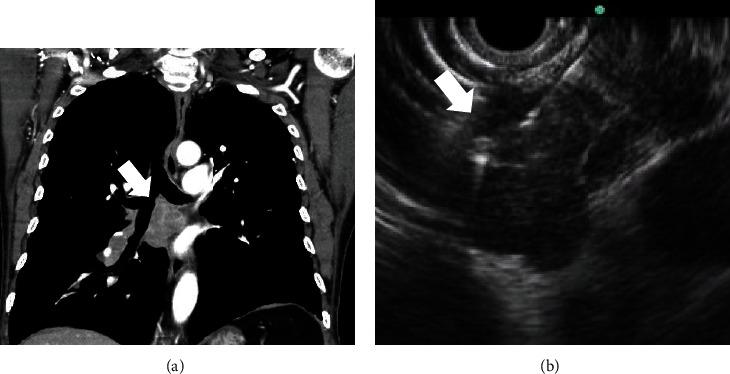

From May 2006 to January 2017, patients with mediastinal lymphadenopathy, who received an EUS-guided trucut biopsy or an FNA biopsy, were retrospectively reviewed. Demographic data, endosonographic characteristics of LNs including size, shape, border, echotexture, and echogenicity, diagnostic yield, and adverse events between the trucut needle group and aspiration needle group were compared.

A total of 69 patients (trucut group, = 33 vs. aspiration group, = 36) were identified. There were no significant differences in demographic data, indication for an EUS-guided biopsy, location of LNs, number of needle passes, and endosonographic features of LNs between the two groups. The sizes of LNs were larger in the trucut group than in the aspiration group (28.9 ± 14.0 mm vs. 21.1 ± 8.8 mm, = 0.007). However, there was no significant difference in the ratio of LNs that were ≥10 mm in both groups. The overall accuracy of the EUS-guided biopsy for the diagnosis of malignant lesions was 79.7% (55/69). There were no significant differences in the histological diagnostic yield of malignant LNs between the two groups. There were no significant procedure-related adverse events in both groups.

The EUS-guided biopsy can be a useful method for histologic evaluation of mediastinal nodal lesions.